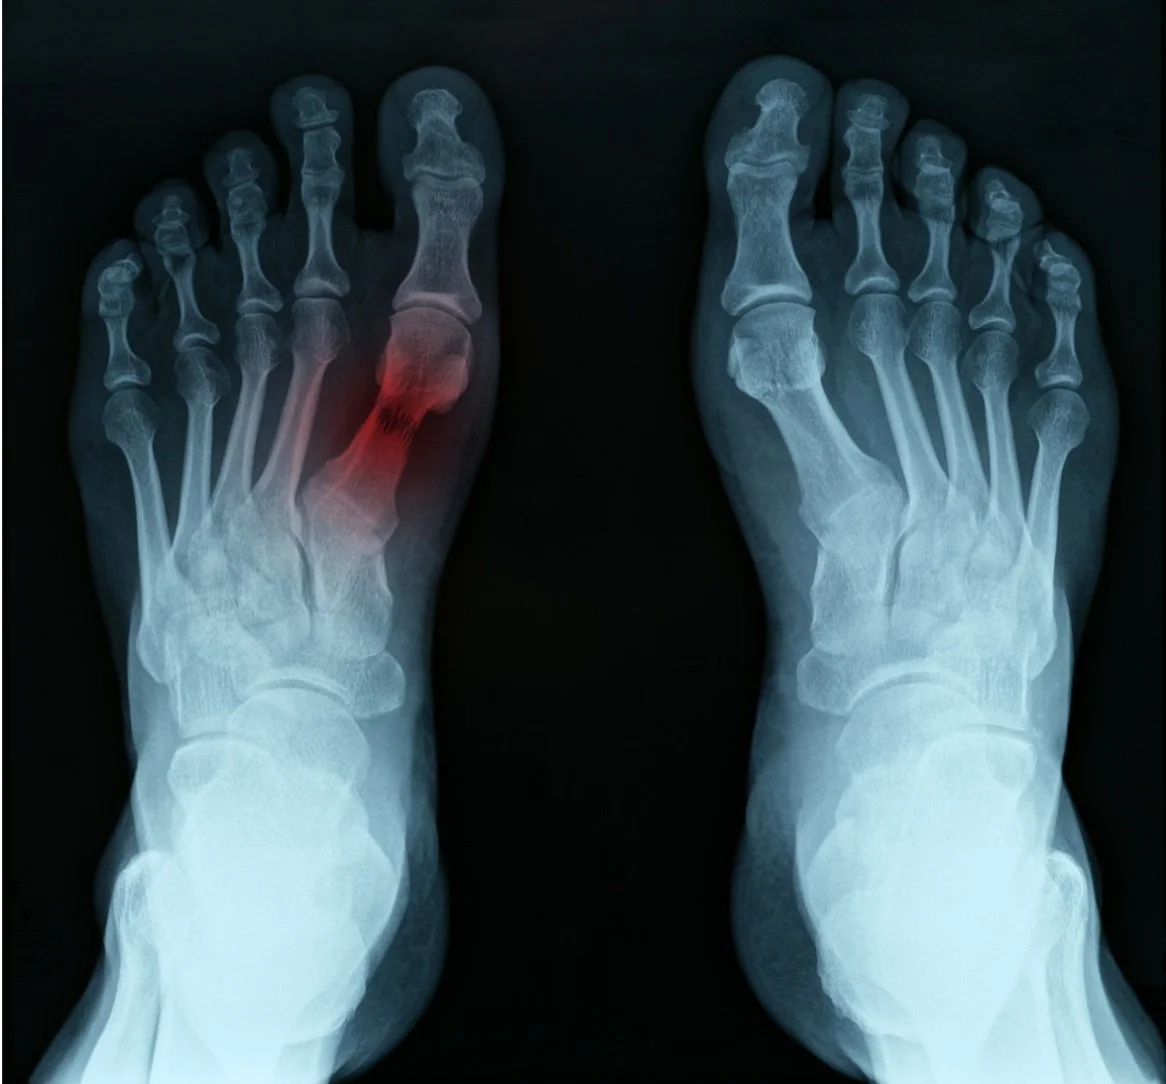

FRACTURES

What is a Stress Fracture?

Stress fractures are tiny cracks that appear in your bones. These injuries are common in the bones in the lower body because these bones are responsible for distributing and bearing your body weight. Feet are particularly vulnerable to stress fractures because they are responsible for absorbing your bodyweight during normal activities—such as walking, running, or jumping.

Symptoms & Causes of Stress Fractures

Stress fractures are usually the result of an overuse injury and are most commonly experienced in runners and other athletes. Stress fractures occur over time due to repetitive forces that occur on weight-bearing bones and supporting muscles. This constant repetition eventually causes small cracks to form in the bone.

Because stress fractures are so small, they typically don’t cause any pain at first. However, over time—with enough repetitive motion—pain can develop in the affected area. While repetition and overuse are the most common causes of stress fractures, other factors contribute to their development. Some of these causes include:

Diagnosis & Treatment of Stress Fractures

To diagnose a stress fracture, your podiatrist will discuss your medical history and gather information about your symptoms. Then, he or she will perform a physical examination where they will check for areas of tenderness and pain. Once located, your podiatrist may recommend imaging tests—like X-rays or an ultrasound—to help confirm the diagnosis.

The treatment depends on the severity of your stress fracture. For mild stress fractures, your doctor will probably recommend non-surgical treatment. Some of these treatments include: